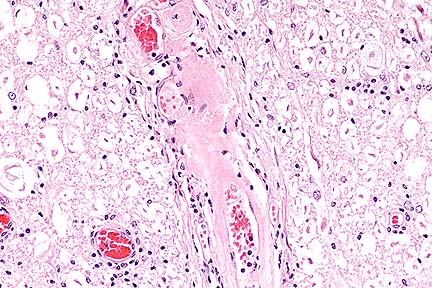

Marked infiltration of the skin of the muzzle by neoplastic lymphocytes in a case of equine epitheioltrophic lymphosarcoma (mycosis fungoides). (HE, 100X, 73K)

Higher magnification of the field shown above, with formation of a intraepithelial vesicle containing neoplastic lymphocytes (Pautrier's microabscess.) (HE, 400X, 71K)

The skin section was taken from the area of the muzzle. The superficial dermis is mildly infiltrated with atypical lymphocytes. They vary in size and they have hyper- convoluted vesicular to hyperchromatic nuclei. Some of these lymphoid cells appear blastic with large vesicular rounded nuclei and prominent nucleoli. Mitotic figures are abundant. The cellular infiltrate consists of some small lymphocytes, neutrophils, macrophages and multinucleated giant cells. The infiltrates of atypical lymphocytes extend into the deep dermis and the subcutis. Furthermore, the lymphoid infiltrate could be found in the epidermis and in the epithelium of hair follicles and adnexal structures. In some places, the intra-epithelial infiltrations form clusters (Pautrier s microabscesses). The dermis is thickened; acanthosis, hyper- and parakeratosis are present. There is focal epidermal necrosis and bacteria and fungal structures (yeasts) are also seen.

The heart tissue sample originates from the heart base. The epicardial fatty tissue and the outer layers of the myocardium are highly infiltrated by atypical lymphocytes, which are similar to those found in the skin.

In this case, the diagnosis of epitheliotrophic lymphosarcoma ( mycosis fungoides ) was based on the following findings: atypical lymphocytes with clefted nuclei, intra-epithelial lymphoid infiltrations arranged singly or in clusters (Pautrier s micro abscesses). Metastasis in various organs is consistent with the late stage of the illness.

AFIP Diagnosis: 1. Skin: Lymphosarcoma, epitheliotrophic, German Warmblood, equine. 2. Heart: Lymphosarcoma.